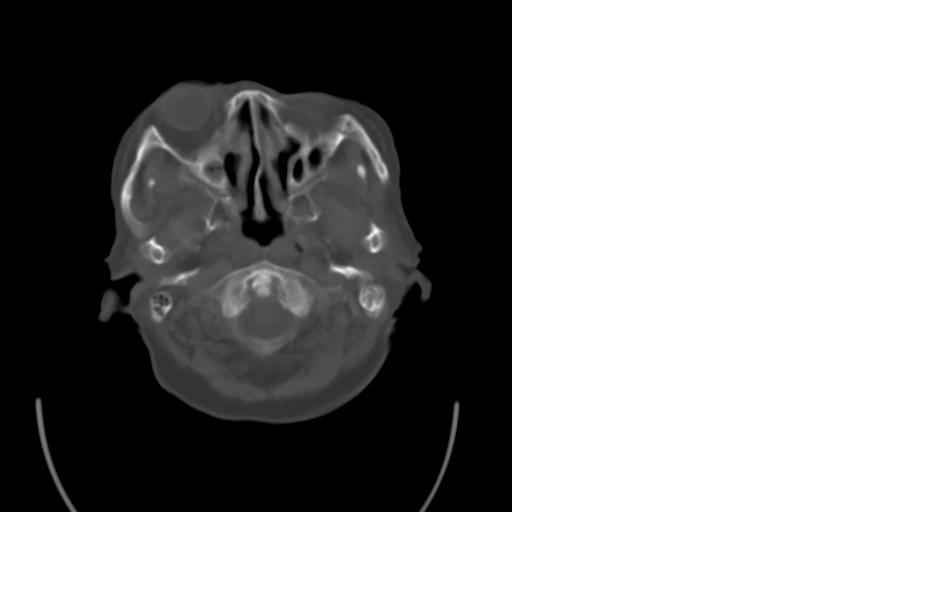

女,77岁,渐进性突眼2年,无其他明显症状

右额窦粘液囊肿,向前累及筛窦并进入眼眶使眼球前突;向下进入颅内右额叶脑质及侧脑室受压

病变应起源于右侧额窦/或额骨板障,肿块周围骨包壳尚完整,呈膨胀挤压改变,右侧眼球受压移位,右侧大脑半球额叶白质受压塌陷,水肿不明显.考虑为良性病变,骨纤维瘤/或骨嗜酸性肉芽肿? 建议增强吧

向前、后破坏颅骨,向后进入颅内,下破坏眶上板进入眶窝,压迫眼球前移,向前内破坏筛窦。

支持:病变的起源我乐意定在右额窦。右额窦粘液囊肿或粘液腺癌累及筛窦、眼眶使眼球前突;向下进入颅内右额叶脑质及侧脑室受压变形。

起原右筛窦或额窦肿块有骨质破坏,1粘液囊肿,2纤维血管瘤待除外.

定位:来源右额窦。定性:良性占位—额窦黏液囊肿。理由1、病灶中心位于右额窦区,侵及筛窦并向下向前压迫眼球2、骨质呈膨胀性改变,骨质弓形变薄但骨壳完整,如为恶性骨质应为侵蚀性破坏3、黏液囊肿好发于筛窦、额窦。